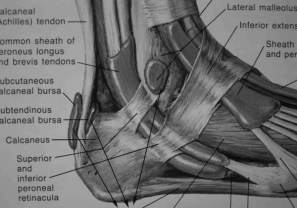

④学习滑膜囊,由前边学习的关节的基本结构关节囊的滑膜层向外突出,引出滑膜囊的由来,由图片讲解滑膜囊的分布位置,引导学生给出滑膜囊的作用。(学生集体回答)

图4-5-14 踝关节滑膜囊

图4-5-15 肩关节滑膜囊